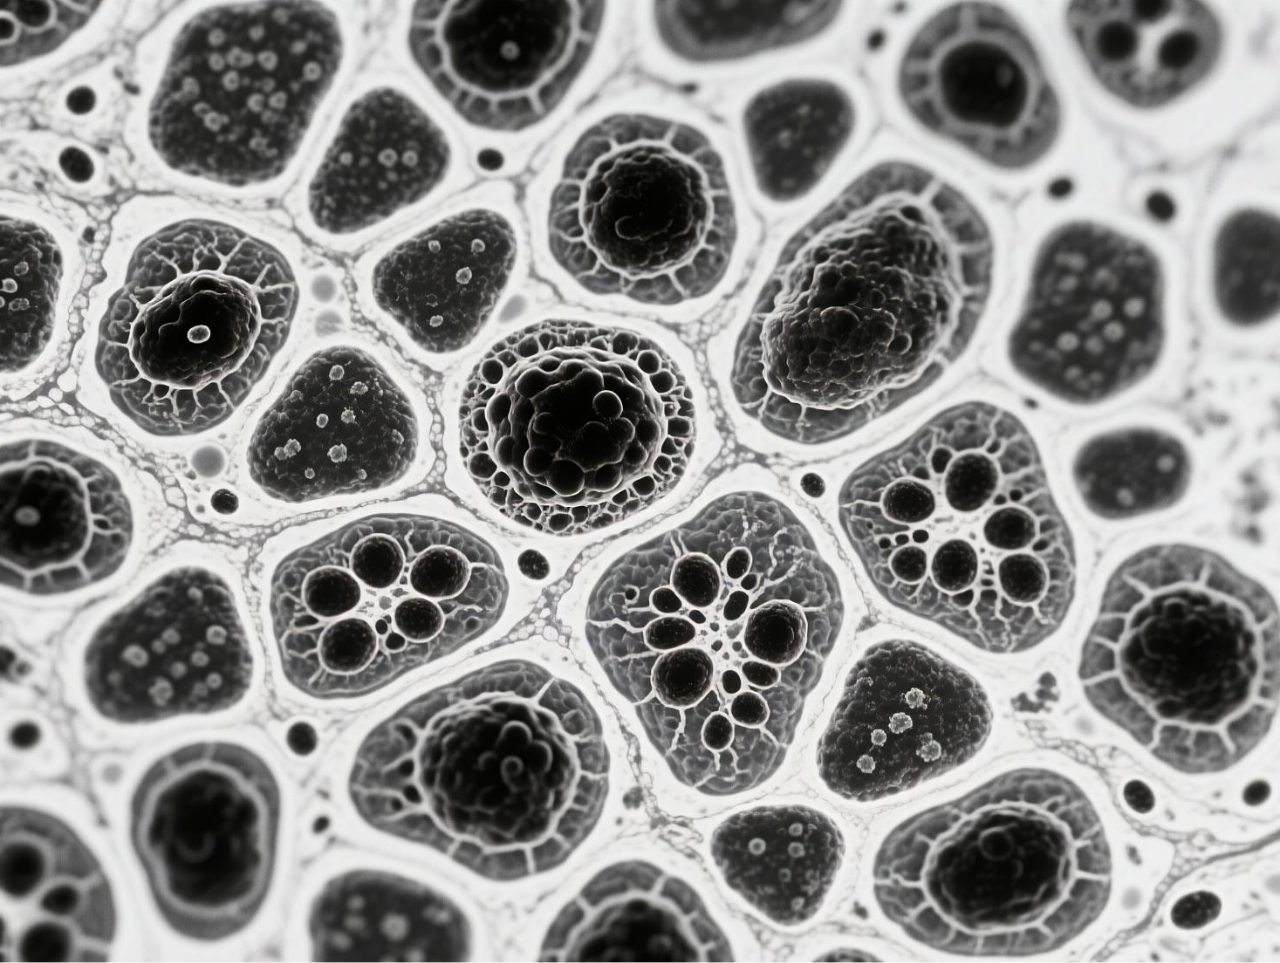

圖 BCG-MBs的制備與表征

臺式掃描電鏡在本研究中發(fā)揮了關(guān)鍵的表征作用,為微氣泡系統(tǒng)的結(jié)構(gòu)驗證提供了直觀而精確的證據(jù)。研究團隊使用澤攸科技ZEM18臺式掃描電鏡對凍干后的BCG-MBs進行金濺射鍍膜處理后,在不同放大倍數(shù)下觀察其表面形態(tài),清晰地展示了微氣泡規(guī)則的球形結(jié)構(gòu)以及BCG在微氣泡表面的不規(guī)則分布狀態(tài)。這一表征不僅確認了微氣泡制備工藝的成功,還直觀揭示了BCG在微氣泡中的物理分布特征,為理解藥物釋放機制提供了結(jié)構(gòu)基礎(chǔ)。掃描電鏡圖像作為重要的形態(tài)學(xué)證據(jù),有力支持了后續(xù)對微氣泡浮力特性、藥物釋放行為及生物效應(yīng)的分析,是連接材料設(shè)計與功能驗證的關(guān)鍵環(huán)節(jié)。